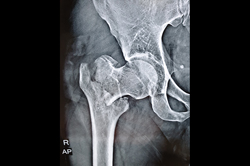

Intertrochanteric Fracture